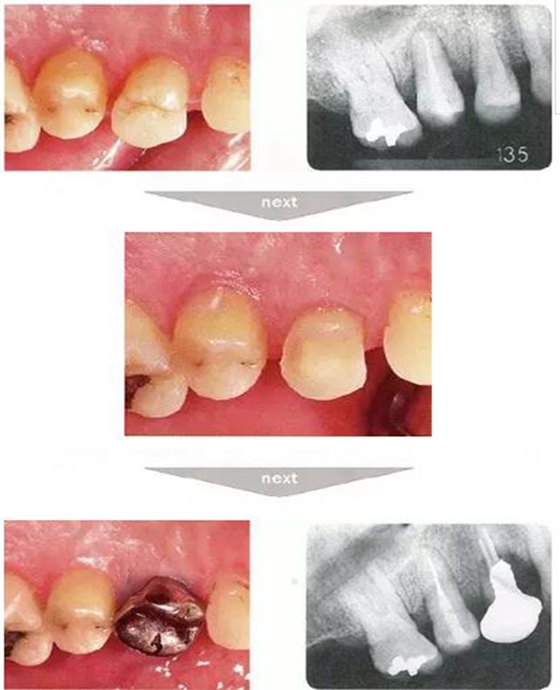

●與外傷相關(guān)的附著喪失①

右下4牙冠牙根破折案例。照片是破折前4個(gè)月拍攝的。牙周袋深度為3mm以下,牙周組織為正常狀態(tài)(右下5是以前由智齒矮小齒移植而來(lái))。破折后,舌側(cè)咬頭破折至傾斜的牙根處,破折片與牙齦相連。

去除破折片進(jìn)行了修復(fù)治療。3年后,上頜腭側(cè)有6mm、近中有4mm的牙周袋。X片可觀察到嚴(yán)重的骨吸收現(xiàn)象??赏茢喑鍪瞧普垡鸬母街鴨适?。